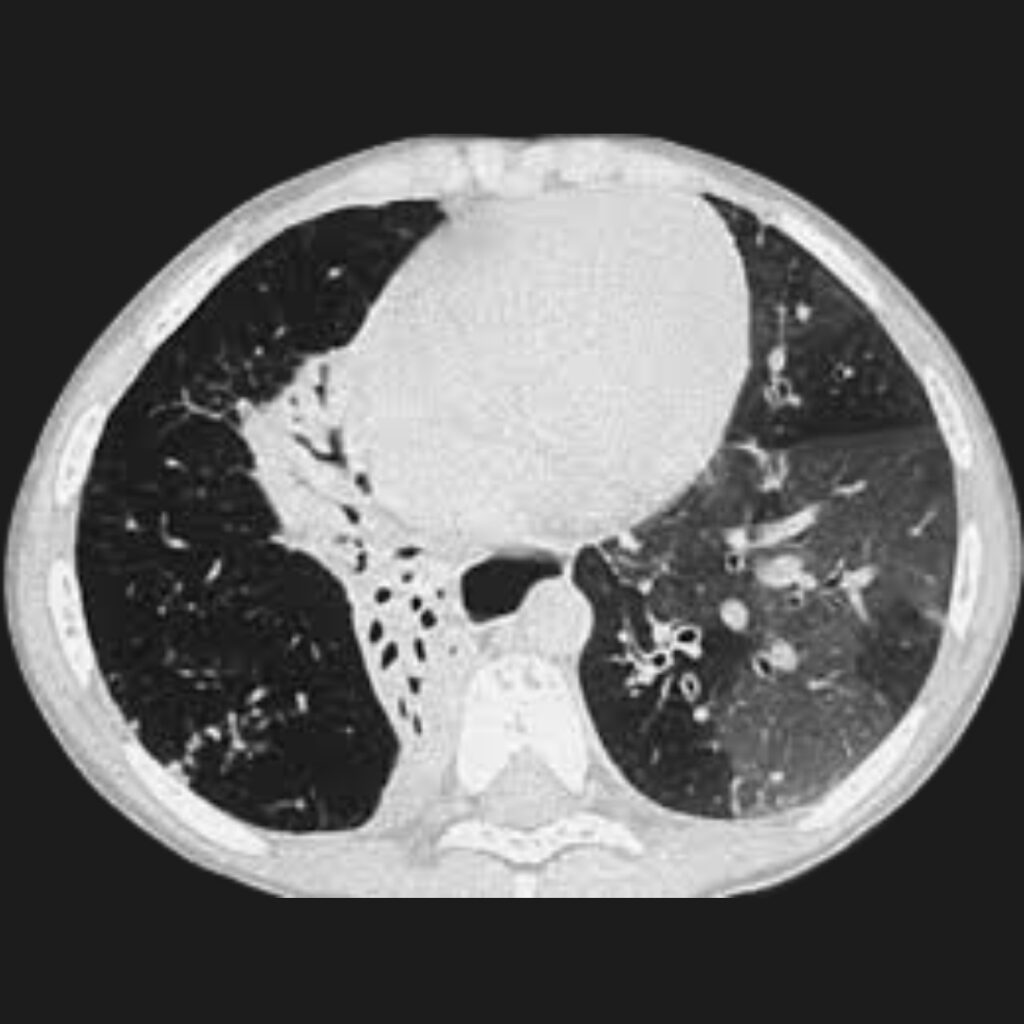

Tomografía computarizada de alta resolución: La tomografía computarizada de alta resolución es una herramienta fundamental en la evaluación de pacientes con sospecha de bronquiolitis obliterante postinfecciosa. Esta técnica permite obtener imágenes detalladas del parénquima pulmonar y de las vías aéreas pequeñas.

- Uno de los hallazgos más característicos es el patrón denominado mosaico de atenuación. Este patrón refleja la presencia de regiones pulmonares con diferente grado de ventilación. Las áreas que reciben menos aire aparecen más densas en las imágenes, mientras que las regiones hiperinsufladas se observan más radiolúcidas.

- Otro hallazgo frecuente es el atrapamiento aéreo, que se hace evidente especialmente durante las imágenes obtenidas en espiración. Además, pueden observarse bronquiectasias, que corresponden a dilataciones anormales de los bronquios, así como engrosamiento de las paredes bronquiales.